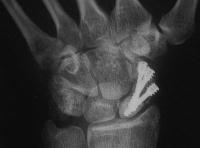

Case 8. Transscaphoid perilunate fracture dislocation...

Click for larger image

Two screws put in dorsally, LT ligament reinforced with a strip of extensor retinaculum left attached to the triquetrium and anchored into the lunate; temporary capitolunate pin.